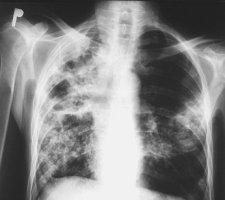

W Polsce codziennie pali tytoń 33,5 proc. dorosłych mężczyzn i 21 proc. dorosłych kobiet - w sumie 8,7 mln dorosłych Polaków. Poza nimi mamy również około miliona okazjonalnych palaczy. Wszyscy razem stanowią ponad 30 proc. populacji - wynika z najnowszego raportu dotyczącego używania tytoniu w P...